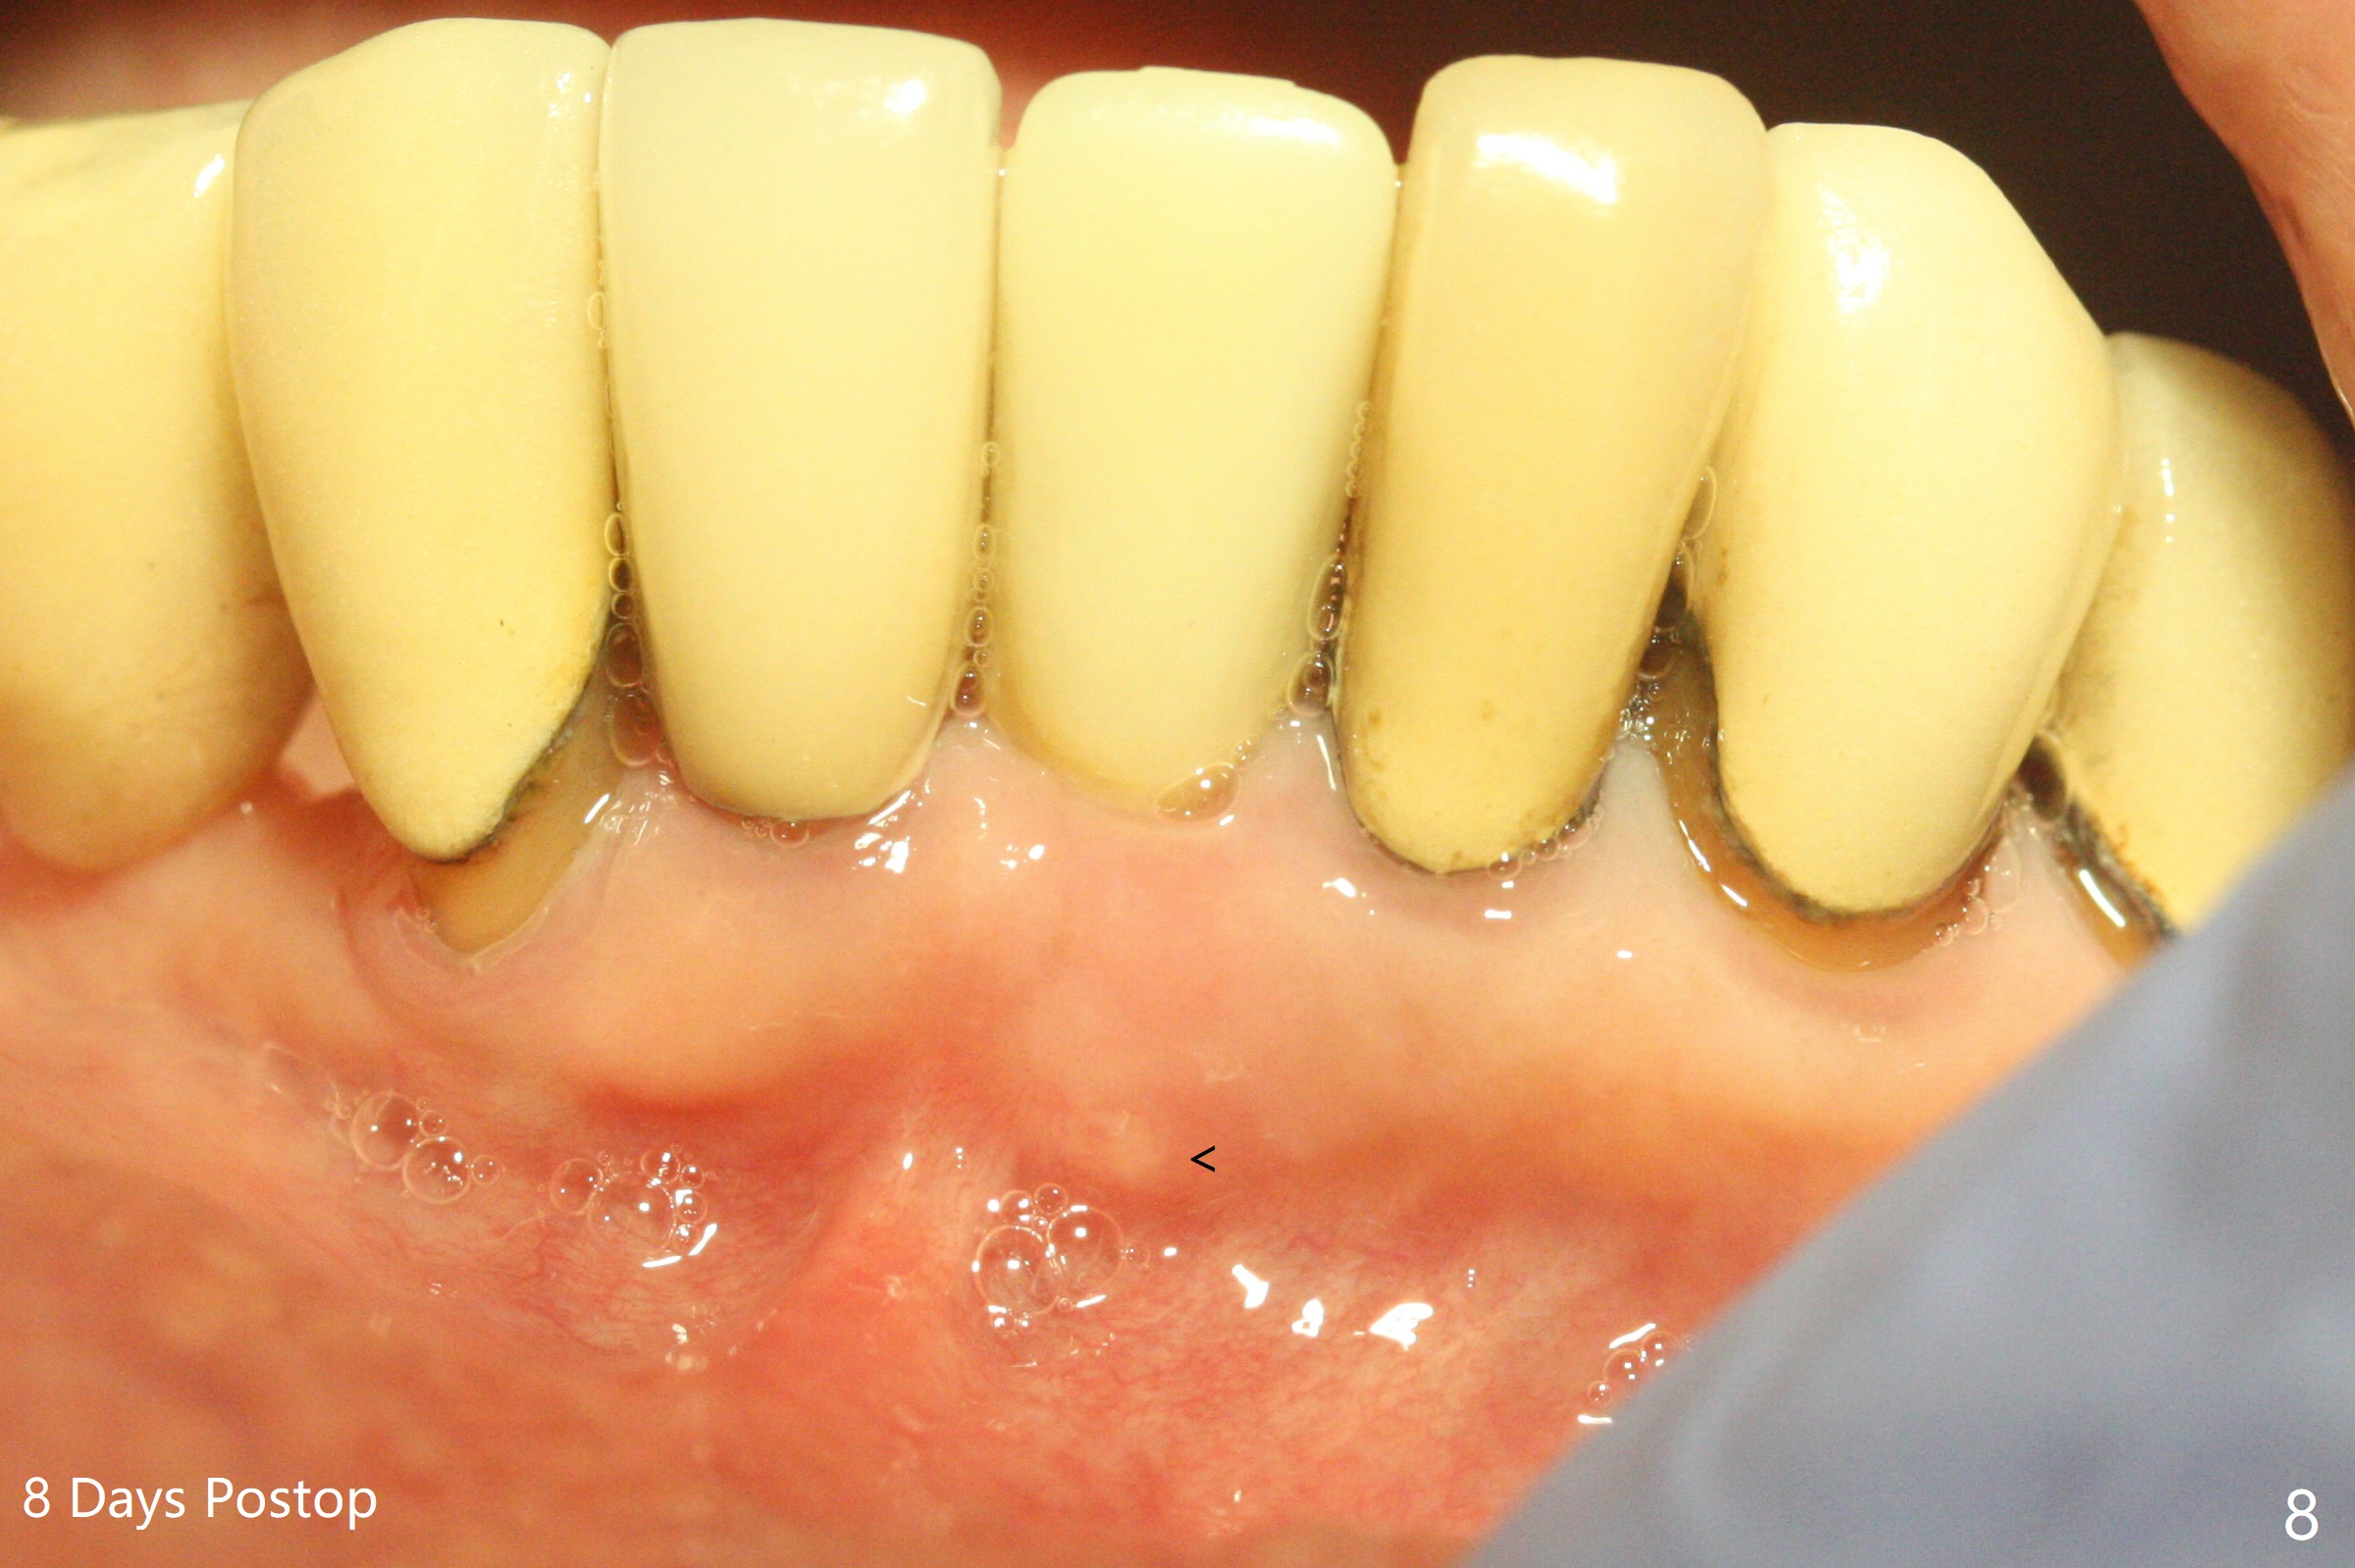

After extraction of the tooth #24 with vertical root fracture (loss of buccolingual plates), osteotomy is initiated with 1.2 mm drill free hand; the trajectory seems satisfactory (Fig.1). With sequential osteotomy, a 2.5x14(2) mm 1-piece implant has difficulty being placed deep (Fig.2), apparently associated with dense bone. Allograft is placed not only mesiodistal (Fig.2,4 *), but also buccolingual (Fig.3,5,6 *) to cover the exposed implant threads. In fact inability to place the implant deep is due to the apex of the implant (Fig.5,6 x) touching the lingual (L) cortical plate. If surgical guide were used, the implant placement difficulty would not occur. The surgery would be shorter and easier. The seemingly easiest implant placement should be assisted with a guide! In addition, preop CT would dictate implant placement in the middle of the socket buccolingual. The lingual (Fig.7 *) and buccal (Fig.8 <) gingiva remains bulky, although asymptomatic, 8 days postop.